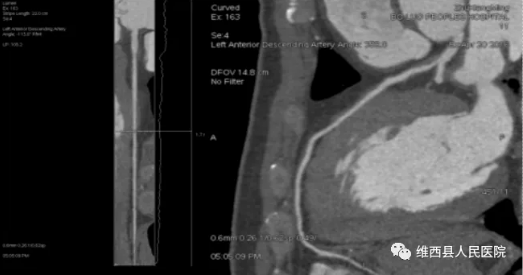

二、冠状动脉CTA

冠脉CTA是经静脉注射造影剂后利用螺旋CT扫描再经过计算机处理重建得出的心脏冠状动脉成像的一种检查方法,能快速且无创的诊断冠脉狭窄、斑块等疾病,对于避免急性心梗等具有重要意义。它不同于介入下冠脉DSA检查,是一项比较成熟的无创检查方式,可以提供与介入性DSA相近的信息。它的创伤小、费用低、门诊即可完成检查。

左前降支起始段轻度狭窄,中段心肌桥

这项新技术不仅可以快速及清晰成像,准确提供冠状动脉管腔的狭窄情况,还可在冠状动脉解剖上提供大量真实信息包括冠状动脉开口的位置、一级分支的走行情况,可以准确显示冠状动脉的位置、长度、心肌桥的厚度、心室及心房的功能,左心室壁的运动情况,进行冠状动脉内斑块的分析,并可以简单而准确地测量各种数据。这一技术项目的开展为患者提供了更宽泛的检查方法。我院将在该新技术的使用过程中提高技术,精益求精,为临床诊断保驾护航,使之成为高危人群的筛查方法及传统血管造影的补充说明。